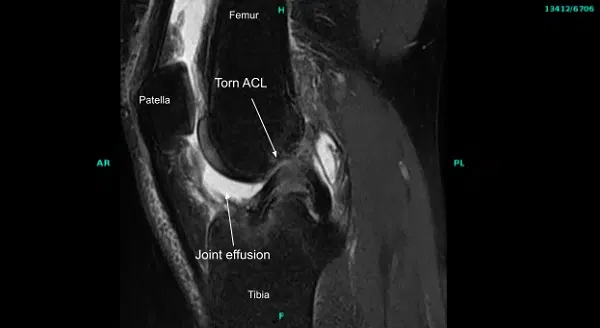

Physical examination was positive for ACL deficiency in the right knee. MRIs of the right knee joint confirmed the injury to ACL. No other pathology was seen. The patient had tried physical therapy in the past with no benefit.

The right lower extremity was prepped and draped aseptically in the usual fashion after application of the tourniquet. Preoperative antibiotics were given. The tourniquet was elevated after Esmarch. Examination under anesthesia showed ACL laxity with a soft ending collaborating with the MRI finding of absent ACL..

Examination of the patellofemoral compartment showed intact cartilage. Examination of the medial patellofemoral compartment showed intact meniscus and cartilage. Examination of the anterior condyle notch showed absent ACL from the proximal attachment.